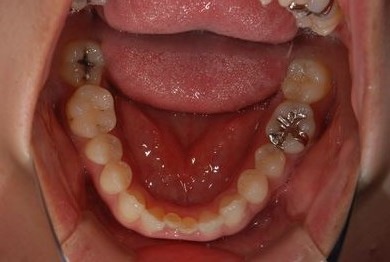

| 主訴 | 下前歯の色が気になるので、ホワイトニングかセラミック治療できれいにしたい。(下前歯2本は乳歯でした) | ||||||||||||||||||||||||||||||||

| 治療方針 | 下顎前歯、乳歯を抜歯し、セラミック治療にて審美的回復を行う。 | ||||||||||||||||||||||||||||||||

| 治療内容 | エンプレスジルコニアフレームオールセラミッククラウンブリッジ4本 | ||||||||||||||||||||||||||||||||